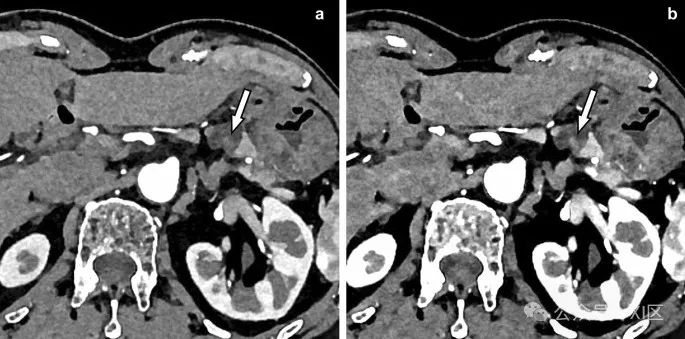

图11 肠系膜静脉中的小血栓(箭头)在光子计数CT图像上可见,分别为70 keV(A)和50 keV(B)。50 keV图像(B)显示血栓的对比度高于70 keV图像(A)。光子计数CT在静脉血栓的可视化方面表现出色。挑战